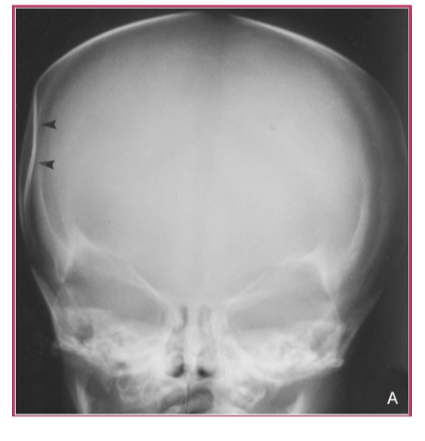

Diagnosis: Depressed Skull Fracture Z

- Conventional skull radiograph showing the typical depressed, ââping-pongââ fracture of the newborn.